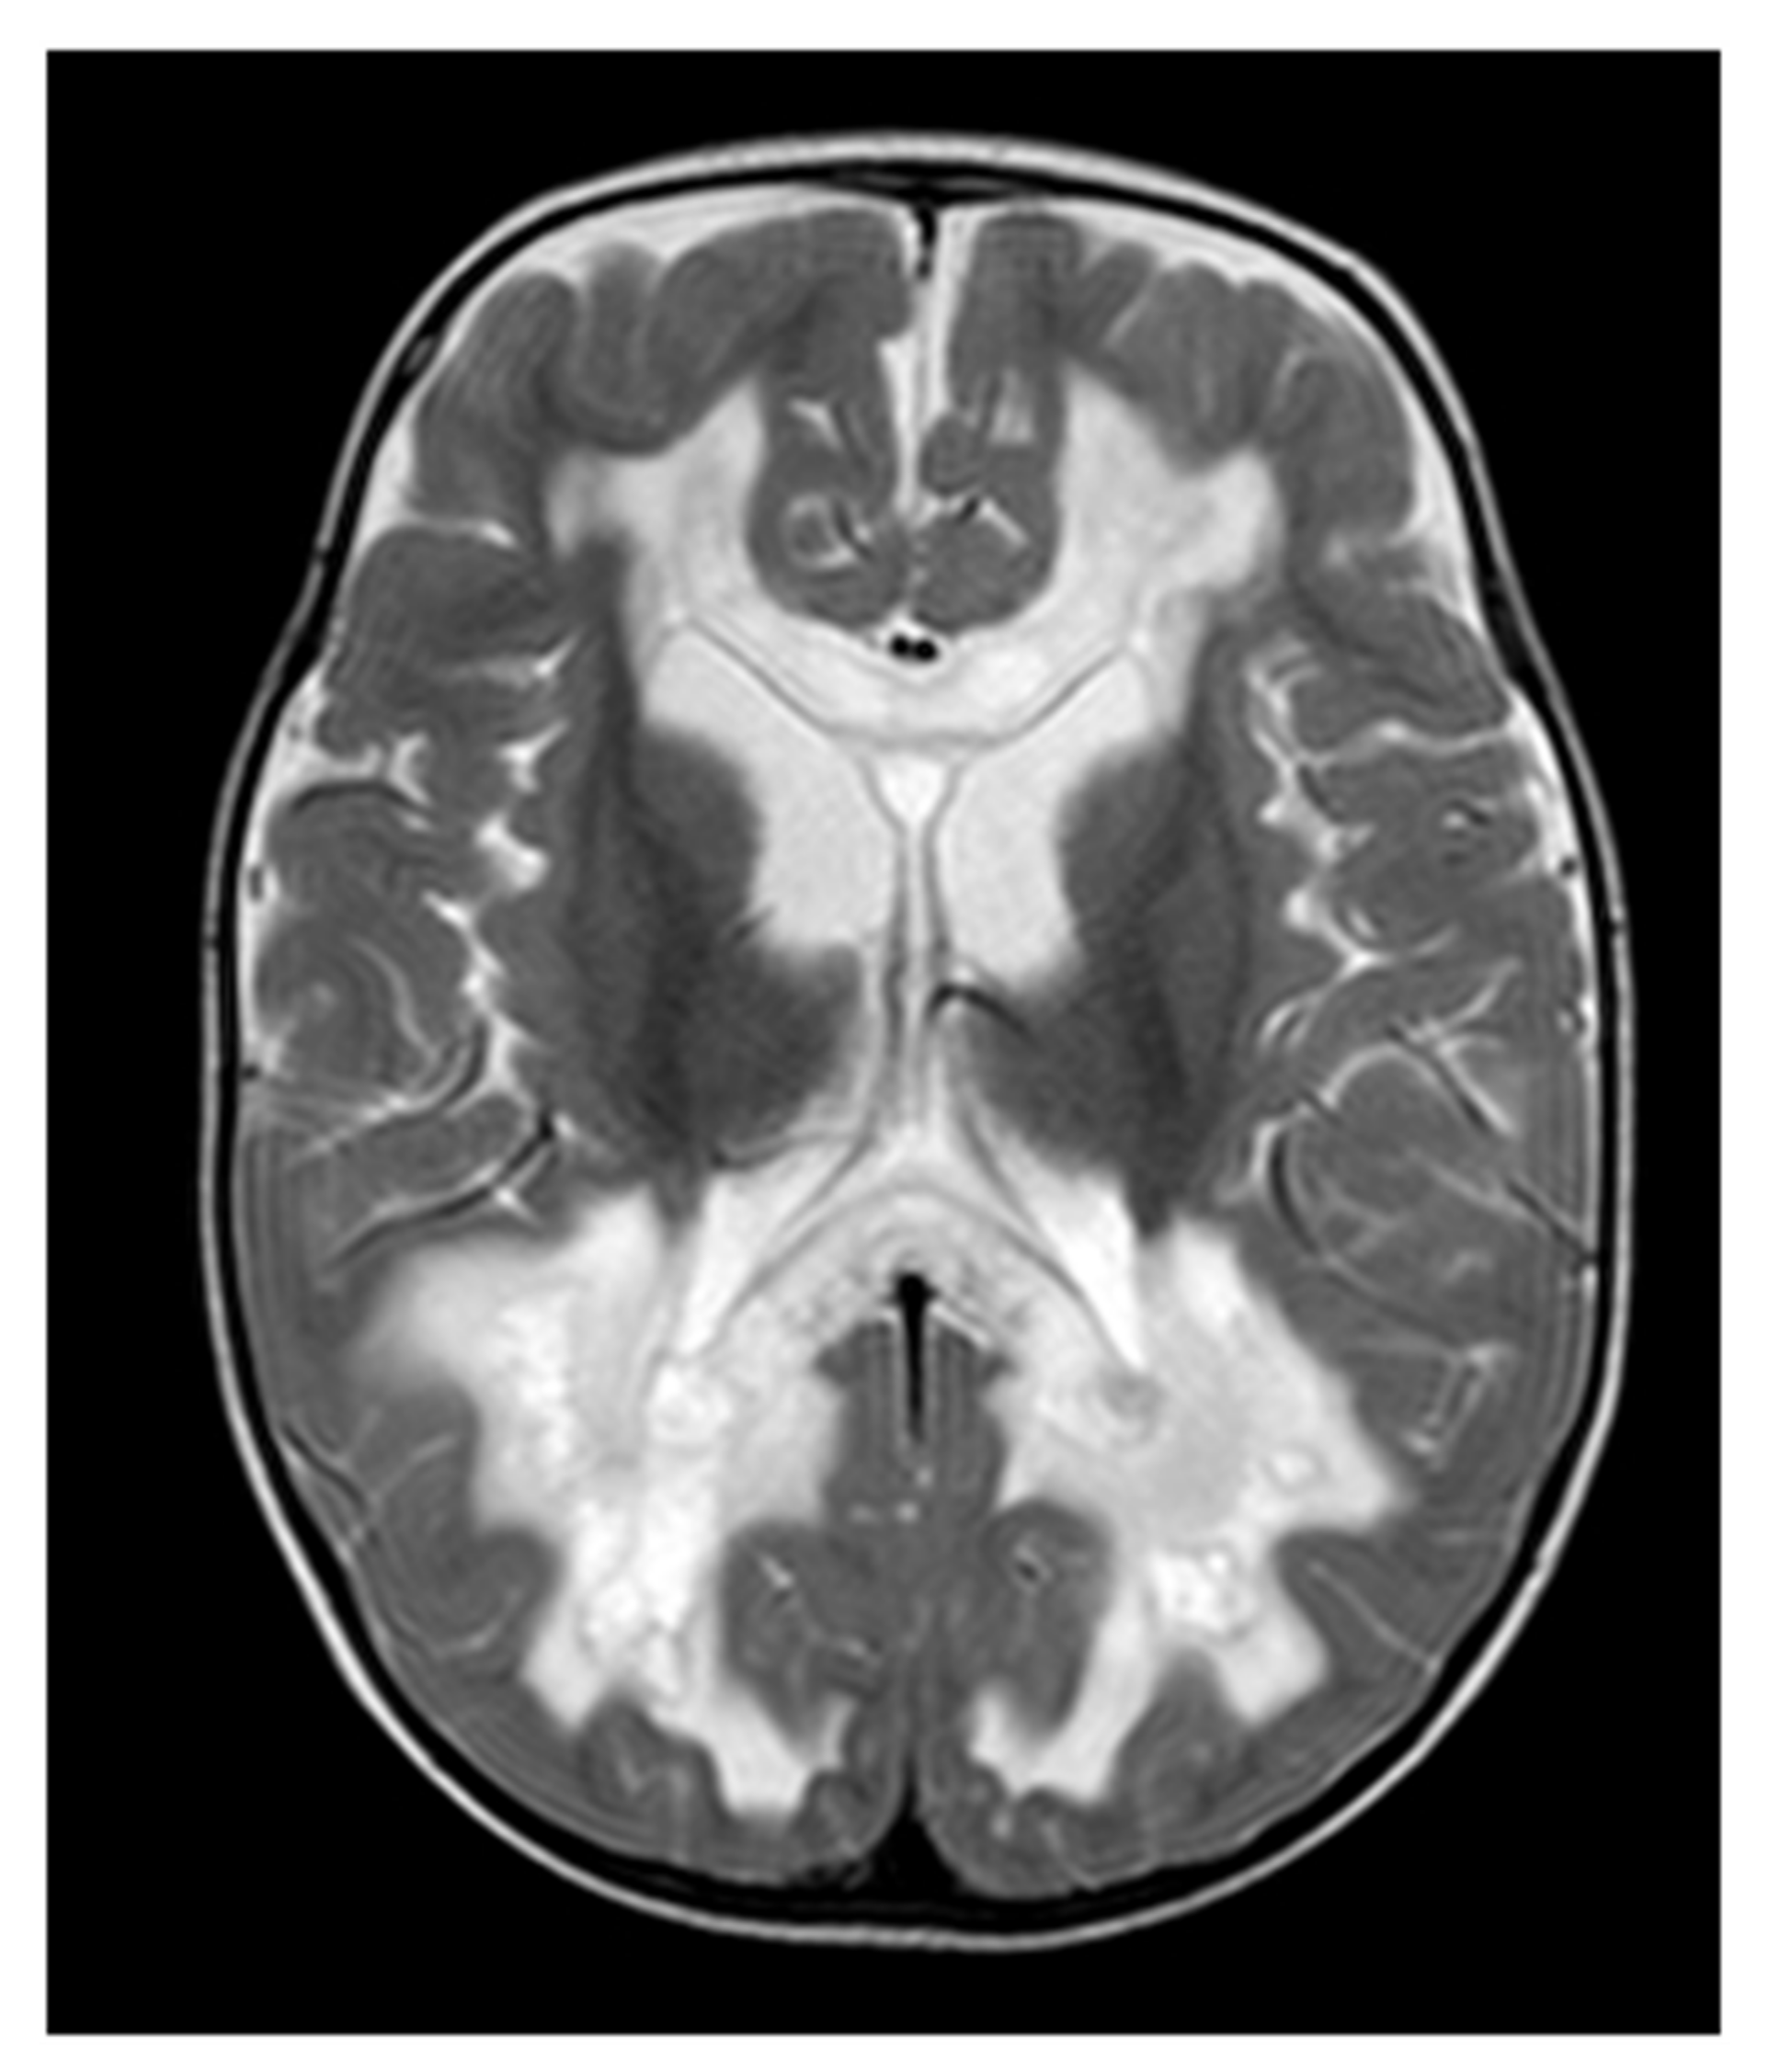

Figure 2.

Neuroimaging in PDSS1 deficiency: Brain MRI (T2-weighted, axial view) of a 24-month-old boy with PSSD1 deficiency. Extensive leukoencephalopathy is visible with cystic white matter lesions in the occipital regions. Other MRI images of this individual were published previously [16].

In one patient clinically presenting with severe developmental delay, seizures, tremor, optic atrophy and hearing impairment, brain MRI at 12 months of age revealed mild cerebral atrophy. At 24 months of age, cystic white matter changes were found. In addition, there were signal abnormalities around the lateral ventricles and commensal fibers consistent with small necrotic or porencephalic cysts [16]. An MRI image of this individual is depicted in Figure 2. The cerebral MRI of another patient at the age of 6 months showed leukencepalopathy and a lactate peak on MR spectroscopy [15]. In the remaining other two patients, no brain abnormalities were found.